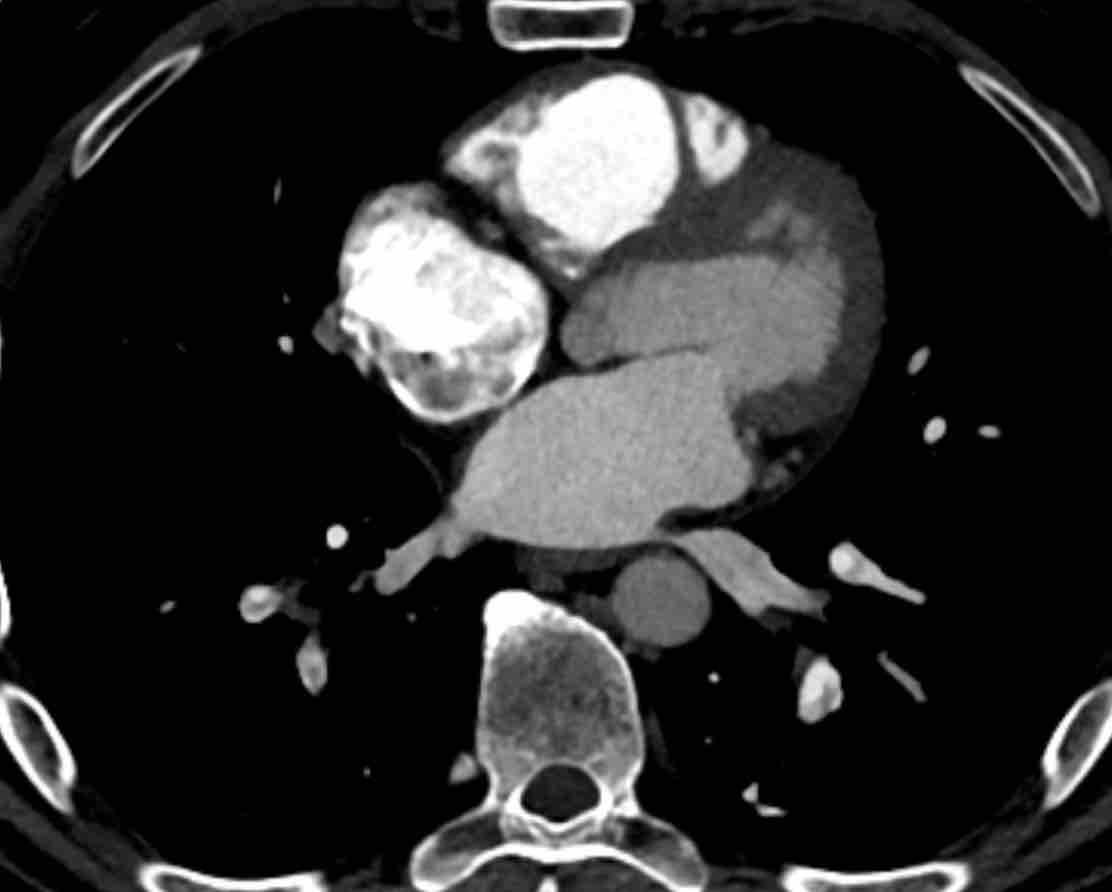

Huyết khối bám thành trong động mạch phổi chính trái ở bệnh nhân mắc bệnh huyết khối tắc mạch mạn tính.

Hình ảnh MIP lát dày của bệnh nhân nam 70 tuổi mắc bệnh huyết khối tắc mạch mạn tính kèm tăng áp động mạch phổi (CTEPH).